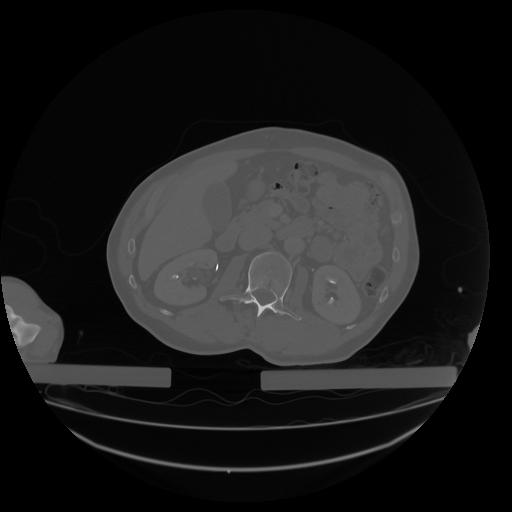

34 CUERPO,CE,Vol,1.0,CUERPO,,